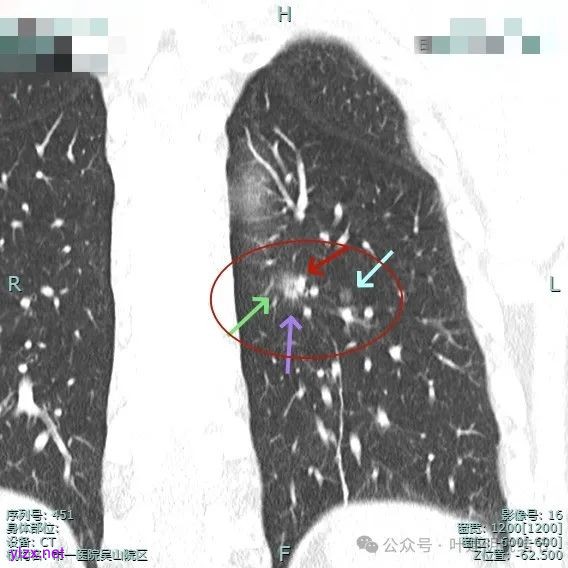

2、手术问题:由于主病灶不纯,血管进入与增粗明显,随访是有风险的,应该考虑手术切除。而若主病灶要切除,那么次病灶离它这么近,应该也要考虑一并切除,不然一是只切主病灶后若次病灶刚好位于切缘处,以后观察有无进展困难,二是以后若仍考虑手术,增加难度。从连续层面看以,主病灶位于后基底段靠近背段处,单纯后基底段切除切缘可能不太够;次病灶则靠近外基底段,如果单纯切除后基底段也不安全。经过科室讨论,意见是可以考虑背段加后基底段切除,后基底段与外基底段之间还要往外基底段侧多切过去点。或者后基底段切除,但离断段间平面时向背段侧扩大切除一部分,往外基底段侧也扩大切除一部分。如果切除基底段,还要往背段切过去点,那下叶余下也不多了。手术方式比较纠结。

手术组再三考虑,由于即使主病灶仍磨玻璃成分为主,是符合指南亚肺叶切除的指征的,如果能想办法定位后楔形切除,不按肺段解剖切,不单手术方便,而且也容易保留更多肺组织。所以与患方商量并沟通后,我们仍选择定位后的楔形切除,术前请影像科沈起钧主任定位,用医用胶定:

上图蓝色箭头所指的是医用定位胶,天蓝色箭头是次病灶,红色箭头是主病灶,设计的切除线如虚线所示。我们打算进胸后确定定位胶所在平面,因为包括两处病灶均在同一平面上,然后我们游离下肺韧带,将后基底段此部分肺组织向下解剖游离开,直到下肺静脉下缘,并贴着下叶静脉边缘往肺实质深面用切割缝合器切开并闭合肺切缘,按CT上大概距离推算,到越过次病灶深度后转向胸肋面,切除该范围内的肺组织。